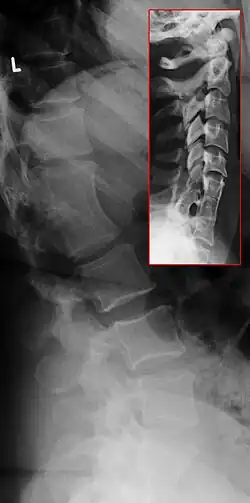

Das Klippel-Feil-Syndrom (auch kongenitale Halswirbelsynostose genannt) ist ein seltenes, angeborenes Syndrom aus einer Fehlbildung der Halswirbelsäule und möglichen weiteren Fehlbildungen. Es ist benannt nach Maurice Klippel (französischer Neurologe und Psychiater, 1858–1942) und André Feil (französischer Neurologe, *1884).[1]

Beim Klippel-Feil-Syndrom kommt es zur Verschmelzung (Synostose) von zwei oder mehr Halswirbeln, gelegentlich auch der gesamten Halswirbelsäule (HWS). Zugrunde liegt eine Störung der Segmentierung der zervikalen Somiten während der etwa 3. bis 8. Woche der Embryonalentwicklung. Die Ätiologie ist nicht geklärt.

In etwa 60 Prozent der Fälle liegen weitere Fehlbildungen der Wirbelsäule vor, meist Skoliose und Kyphose. Das Syndrom kann auch an mehreren Abschnitten der Wirbelsäule gleichzeitig auftreten (vgl. Röntgenbild). Ein Drittel der Patienten hat Fehlbildungen des Harntrakts. In 20 bis 30 Prozent der Fälle findet man einen ein- oder beidseitigen Hochstand des Schulterblattes (Sprengel-Deformität). Etwa 14 Prozent der Patienten haben angeborene Herzfehler.[2]

In der Diagnostik des Klippel-Feil-Syndroms sind standardisierte Röntgenaufnahmen der Halswirbelsäule oft nicht möglich, weil die vorgesehene Standardposition vom Patienten aufgrund der Fehlbildung nicht eingenommen werden kann. Unterkiefer, Hinterhauptsbein und Foramen magnum können sich auf die Halswirbel projizieren. Seitliche Schichtaufnahmen in Beugung (Flexion) und Streckung (Extension) können – insbesondere bei Kindern, bei denen die Epiphysenfugen noch nicht geschlossen sind – hilfreich sein. Schnittbildgebungen wie Kernspintomographie (sollte aufgrund fehlender Strahlenbelastung besonders im Kindesalter vorgezogen werden) und Computertomografie sind besonders geeignet zur Beurteilung, ob eine Kompression von Nervenwurzel oder Rückenmark vorliegt.